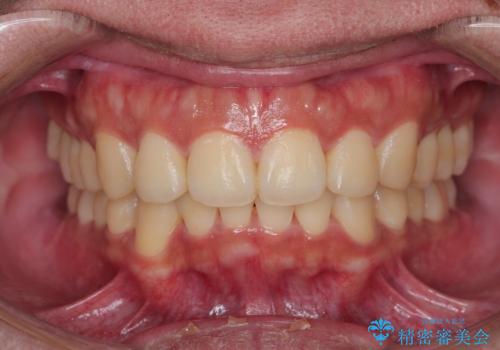

がたつきが気になる。インビザラインでスッキリ。

がたつきもなくなりスッキリした歯並びになりました。

がたつきが無くなると歯ブラシがしやすくなり汚れが溜まりにくい口腔環境ができます。